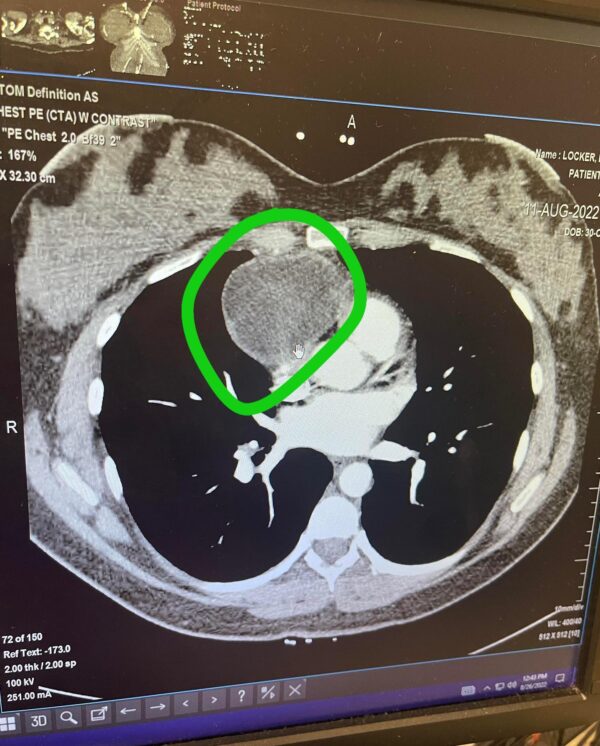

Brittany avait une masse dans la zone située entre ses poumons, le médiastin antérieur, mesurant 7 cm sur 7 cm. Elle pouvait être cancéreuse ou non, ont dit les médecins, qui lui ont conseillé de se faire suivre immédiatement.